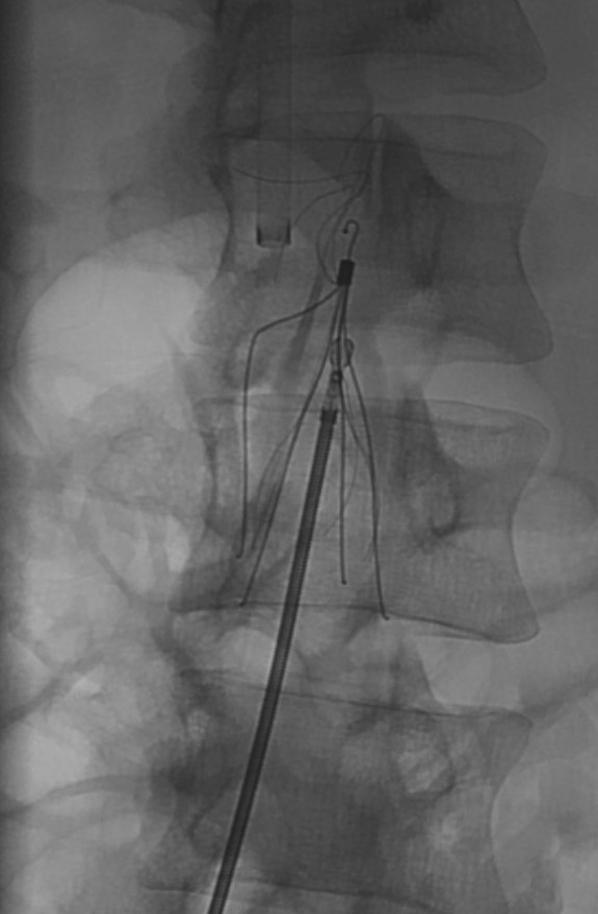

Inferior vena cava filters are important tools used to help prevent life-threatening pulmonary embolisms in hospitalized patients with contraindications to pharmacological prophylactic anticoagulation. This is a case report of a patient who had an inferior vena cava filter placed after a traumatic subdural hematoma. He made a complete recovery but was lost to follow-up until he presented 1825 days after filter deployment with abdominal pain discovered to be from penetration of the filter tines outside the lumen and into adjacent structures. We describe a case complicated by fibrotic tine entrapment with penetration to surrounding structures and discuss the technical approach used to free and eventually remove the long-standing filter.